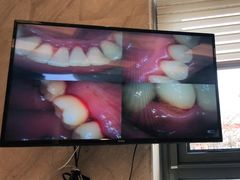

• 劲松口腔医院(蓝色港湾院)

• -劲松口腔医院(蓝色港湾院)

劉大白winter | 21-12-12